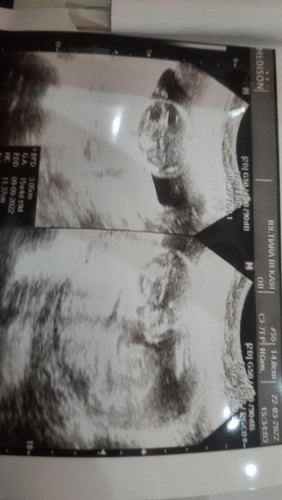

aq kehamilan 8 minggu, muntah terus sejak tau hamil ampe skrng berat badan turun terus udh 4kg, kasian bgt ma anak² ku ga ke pegang, aku nya lemes, mual muntah, cuma enak di bawa rebah, klo aktivitas muntah nya dateng trs, tolong kasih saran² nya ya mam#mohonbantujawabbunda #Sharingdong_Bund #sharing #tolongbagisemangat